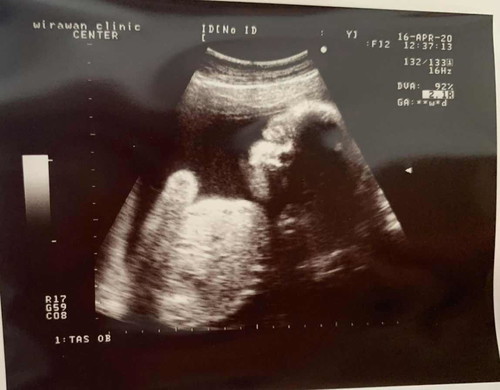

สอบถามหน่อยค่ะ แม่ๆบ้านไหนเป็นบ้าง อายุครรภ์ 6 เดือน แต่มือเท้าบวม มากๆเลย มีวิธีจัดการกับการชอบทานหวานอย่างไร บ้างคะ พอดีน้ำตาลเกินน่ะค่ะ